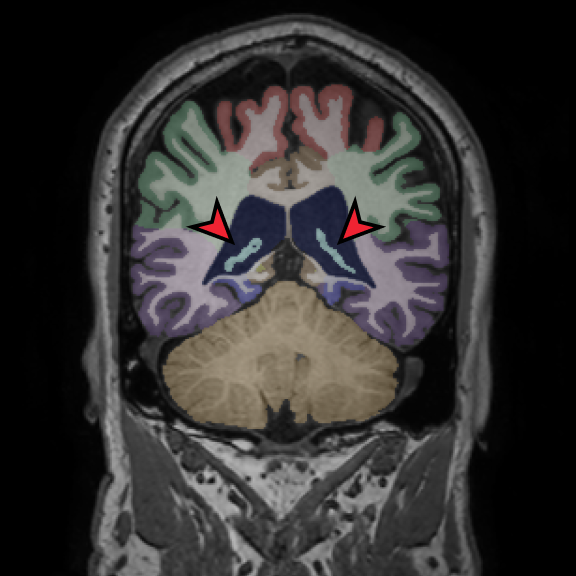

Retrospective brain volumetric analysis in a female patient diagnosed with Alzheimer’s disease at age 77 showed progressive brain atrophy over a 5-year period. The scans demonstrate temporal cortical atrophy with marked ex-vacuo enlargement of the lateral ventricles.

PATIENT

Female patient diagnosed with Alzheimer's Disease at Age 77

Analysis period

5 years

regions of interest

Temporal cortex

Hippocampus

Inferior lateral ventricles

Age 72

Age 74

Age 77

Lateral ventricle